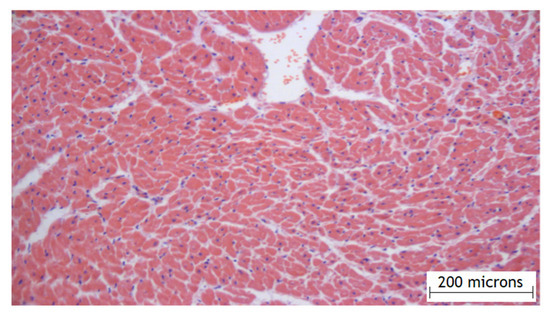

2.1. Results of the Experimental Part

- Group 1 (n = 8)—the dose of amiodarone in hydrogel was 1 mg;

- Group 2 (n = 11)—the dose of amiodarone in the hydrogel was 3 mg;

- Group 3 (n = 7)—the dose of amiodarone in the hydrogel was 6 mg;

- Group 4 (n = 10) control group—the application of the hydrogel material without amiodarone;

- Group 5 (n = 10)—group with an intravenous form of amiodarone at the dose of 60 mg.